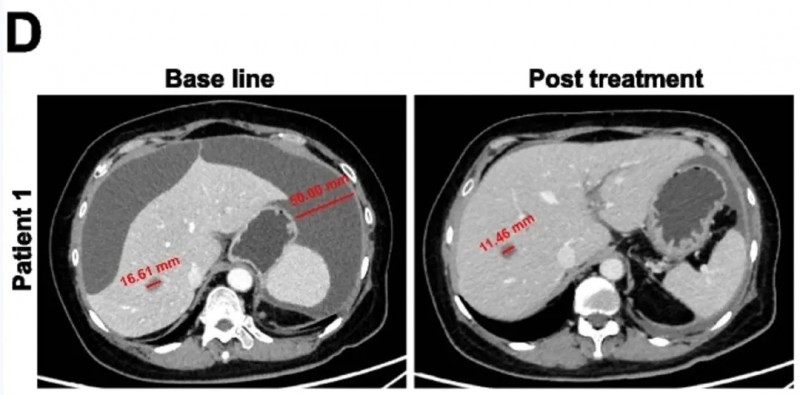

值得关注的是,两位患者的疗效尤为突出:患者1肝转移灶缩小31%,且腹腔积液完全消失;患者2可测量病灶总最大直径缩小42%(详见下图)。

▲图源“BMC”,版权归原作者所有,如无意中侵犯了知识产权,请联系我们删除